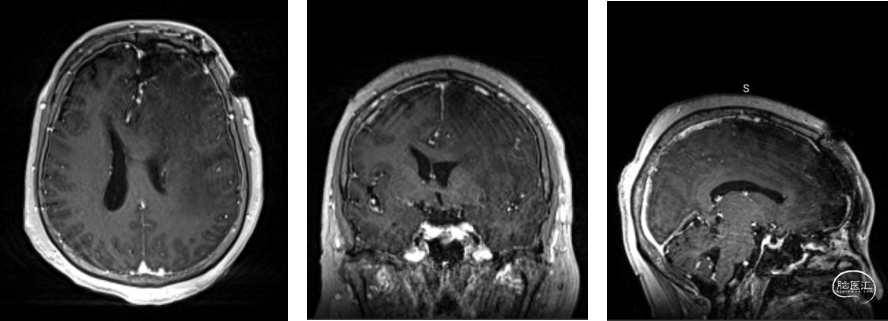

入院后增强头颅MRI影像学资料:

术前增强头颅MRI提示:左侧额叶占位,大小约3.8x3.6x3.9cm,增强扫描呈明显强化,其内见囊变区,伴瘤周水肿,中线结构右偏约1.8cm。考虑肿瘤性病变合并大脑镰下疝形成可能。